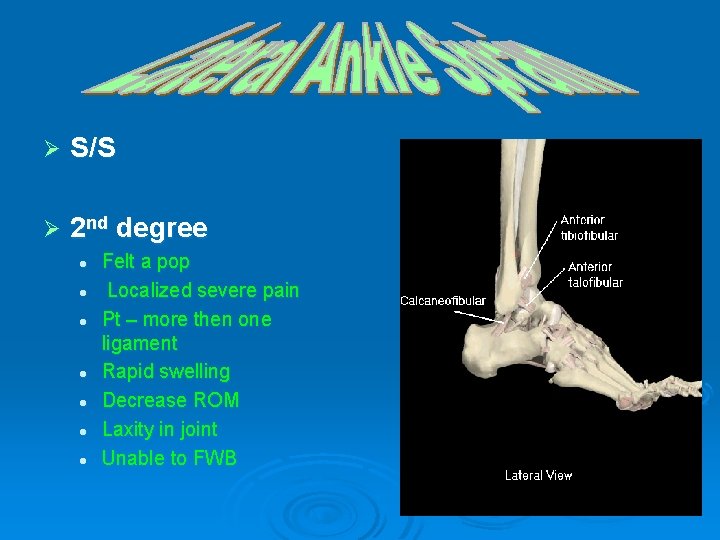

Ø S/S Ø 2 nd degree l l l l Felt a pop Localized severe pain Pt – more then one ligament Rapid swelling Decrease ROM Laxity in joint Unable to FWB